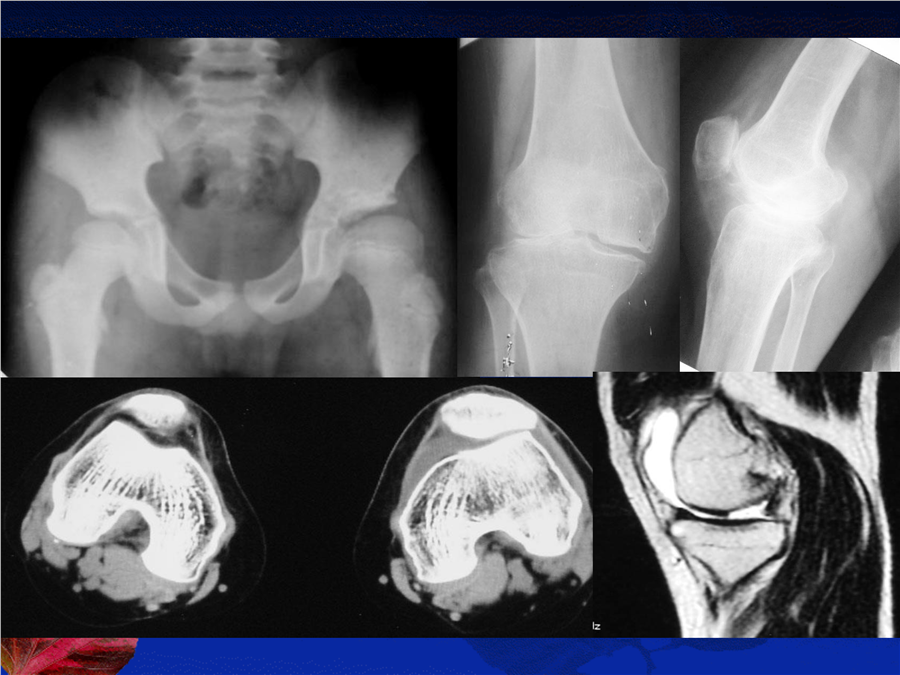

骨关节系统